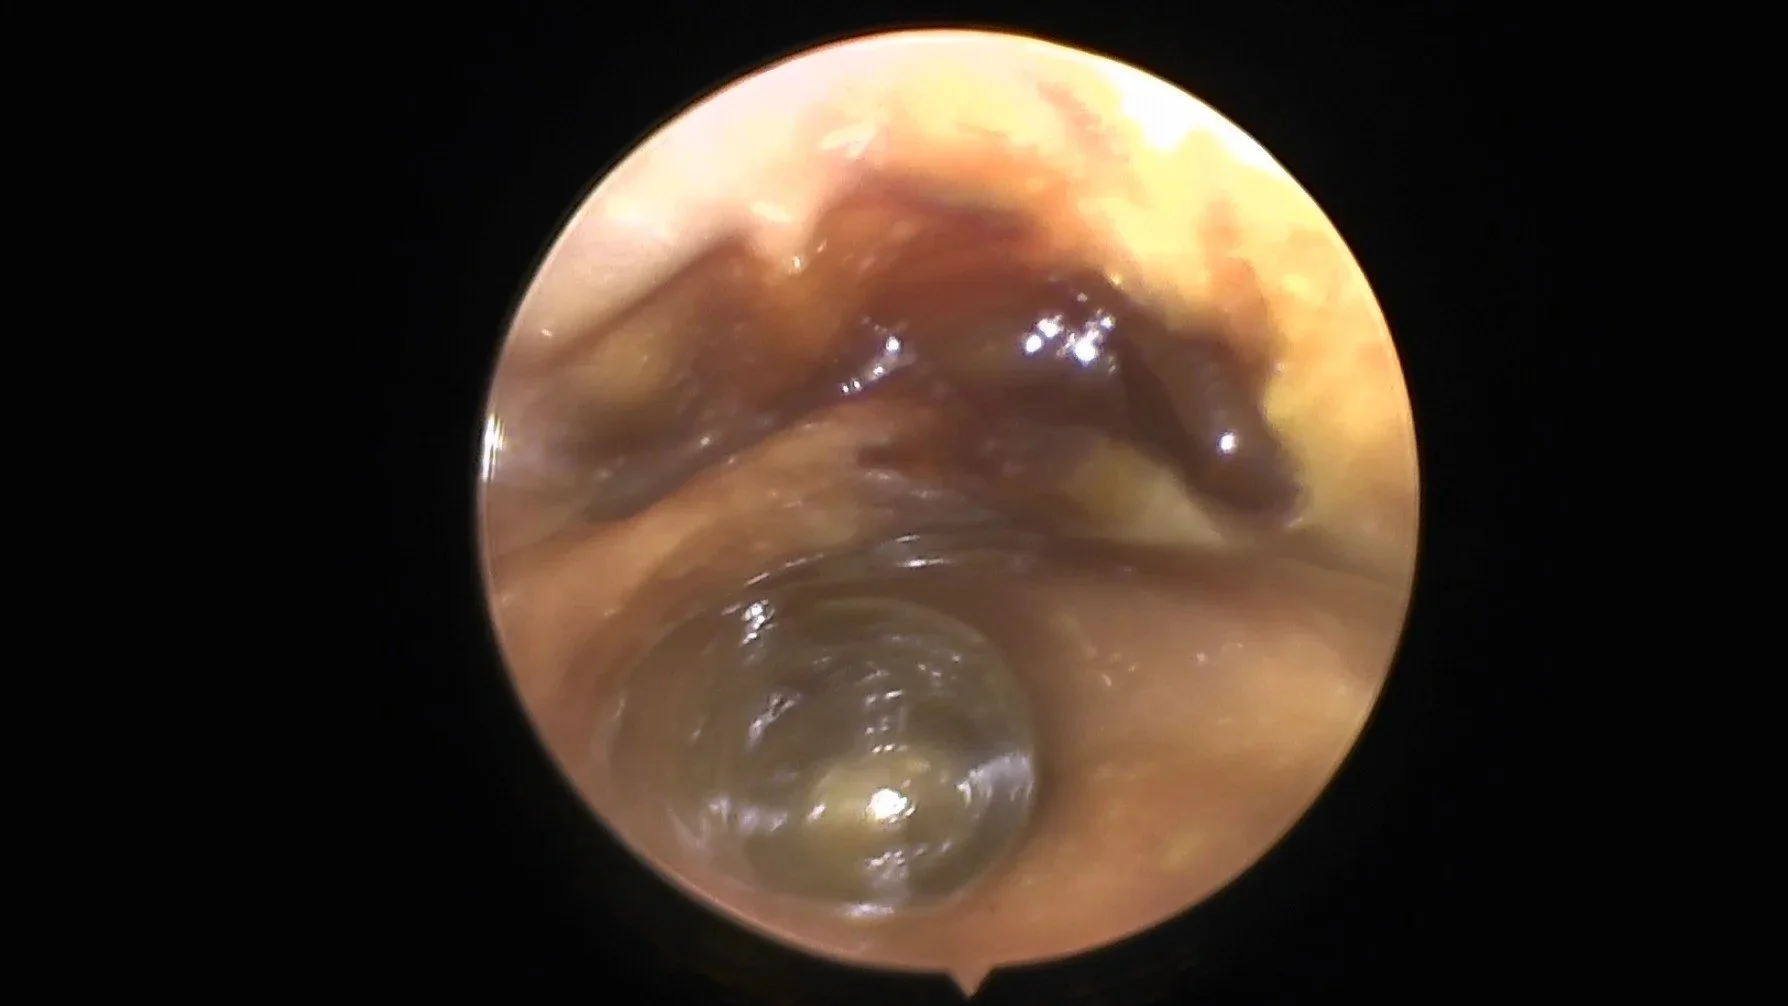

An inflamed and thickened tympanic membrane visualised during an ear flush.

Otitis Media

We can perform a myringotomy for sample collection for culture and sensitivity, followed by a gentle but thorough lavage of the bulla. CT prior to treatment is preferred and we can arrange this if requested.